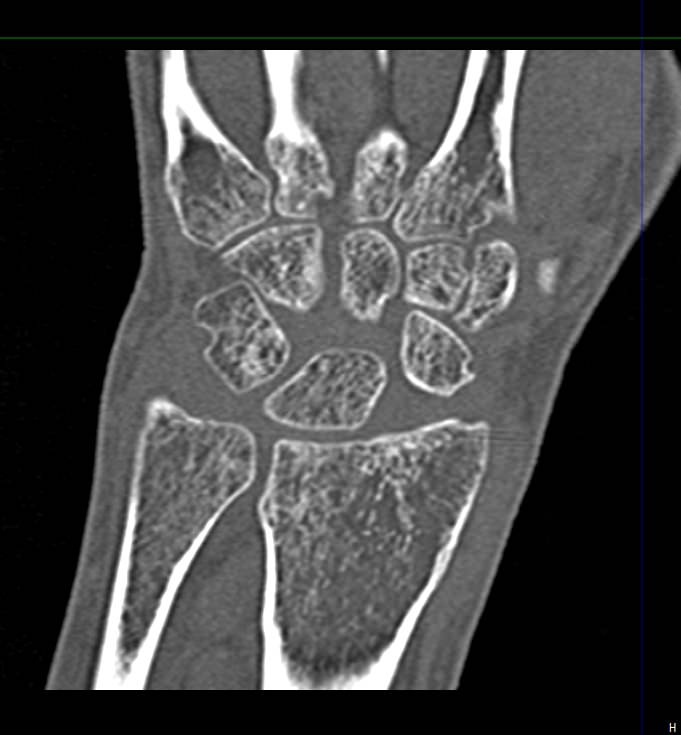

Лучезапястный сустав имеет сложное строение. Это комбинированное сочленение между костями предплечья и кистью руки. Сустав имеет множество анатомических структур, включая мелкие кости запястья (трехгранную, полулунную, ладьевидную, гороховидную, кость-трапецию, трапециевидную, головчатую и крючковидную), а также внутрисуставные диски, связки, мышцы и сухожилия, обеспечивающие гибкость и высокую подвижность сустава.

Метод КТ основан на использовании ионизирующего излучения и способности тканей поглощать рентгеновские лучи. Костные ткани обладают высокой плотностью и способны активно поглощать рентгеновские лучи, поэтому они хорошо видны на снимках КТ. В отличие от обычного рентгена компьютерный томограф послойно сканирует исследуемую область в нескольких плоскостях, благодаря чему получаются снимки в мельчайших подробностях. Затем с помощью цифровой обработки данных, полученных при КТ-сканировании, создаются объемные модели области исследования.

Таким образом, мультиспиральная компьютерная томография позволяет оценить состояние всех структур лучезапястного сустава, выявить травматические повреждения, признаки воспалительных заболеваний, диагностировать аномалии развития и опухолевые образования. При травмах на снимках и трехмерных изображениях хорошо видны фрагменты костных отломков, эти данные используются при подготовке к оперативным вмешательствам. После операции результаты КТ позволяют оценить правильность репозиции костных структур, выявить послеоперационные осложнения, отследить в динамике процесс восстановления тканей.